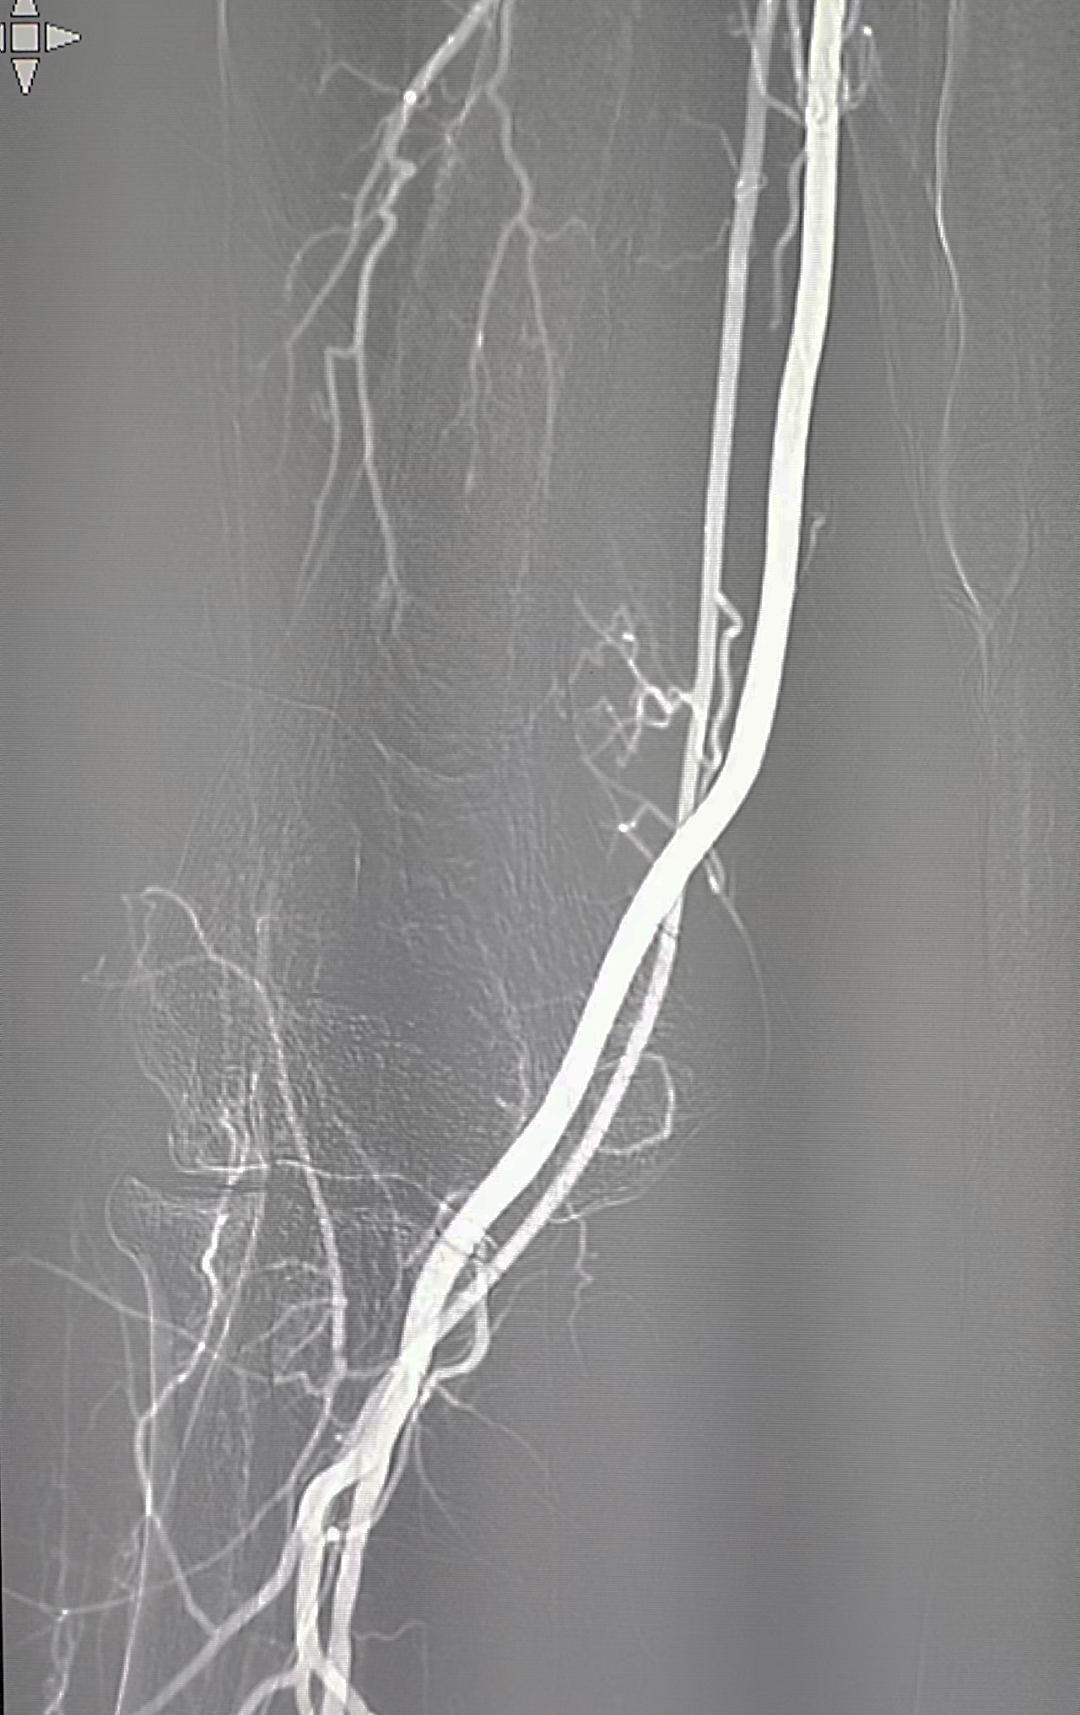

置入泥鳅导丝后退出短鞘,交换6F Epath长鞘在路图下上行至右侧锁骨下动脉。

利用导丝直接超选左侧颈总动脉开口并将导丝头端置于左侧颈外动脉,引导Epath上行至左侧颈总动脉主干。

保护伞上行越过狭窄段并打开,经尾丝引入6*30mm球囊至狭窄处扩张至8atm。

排空球囊后造影示狭窄改善明显,撤出球囊后交换7*40mm Wallstent支架至病变部位打开。

造影示支架打开良好,贴壁良好,病变节段覆盖完全,回收保护伞,再次造影示远端终末血管无栓塞,撤除治疗系统,手术结束。